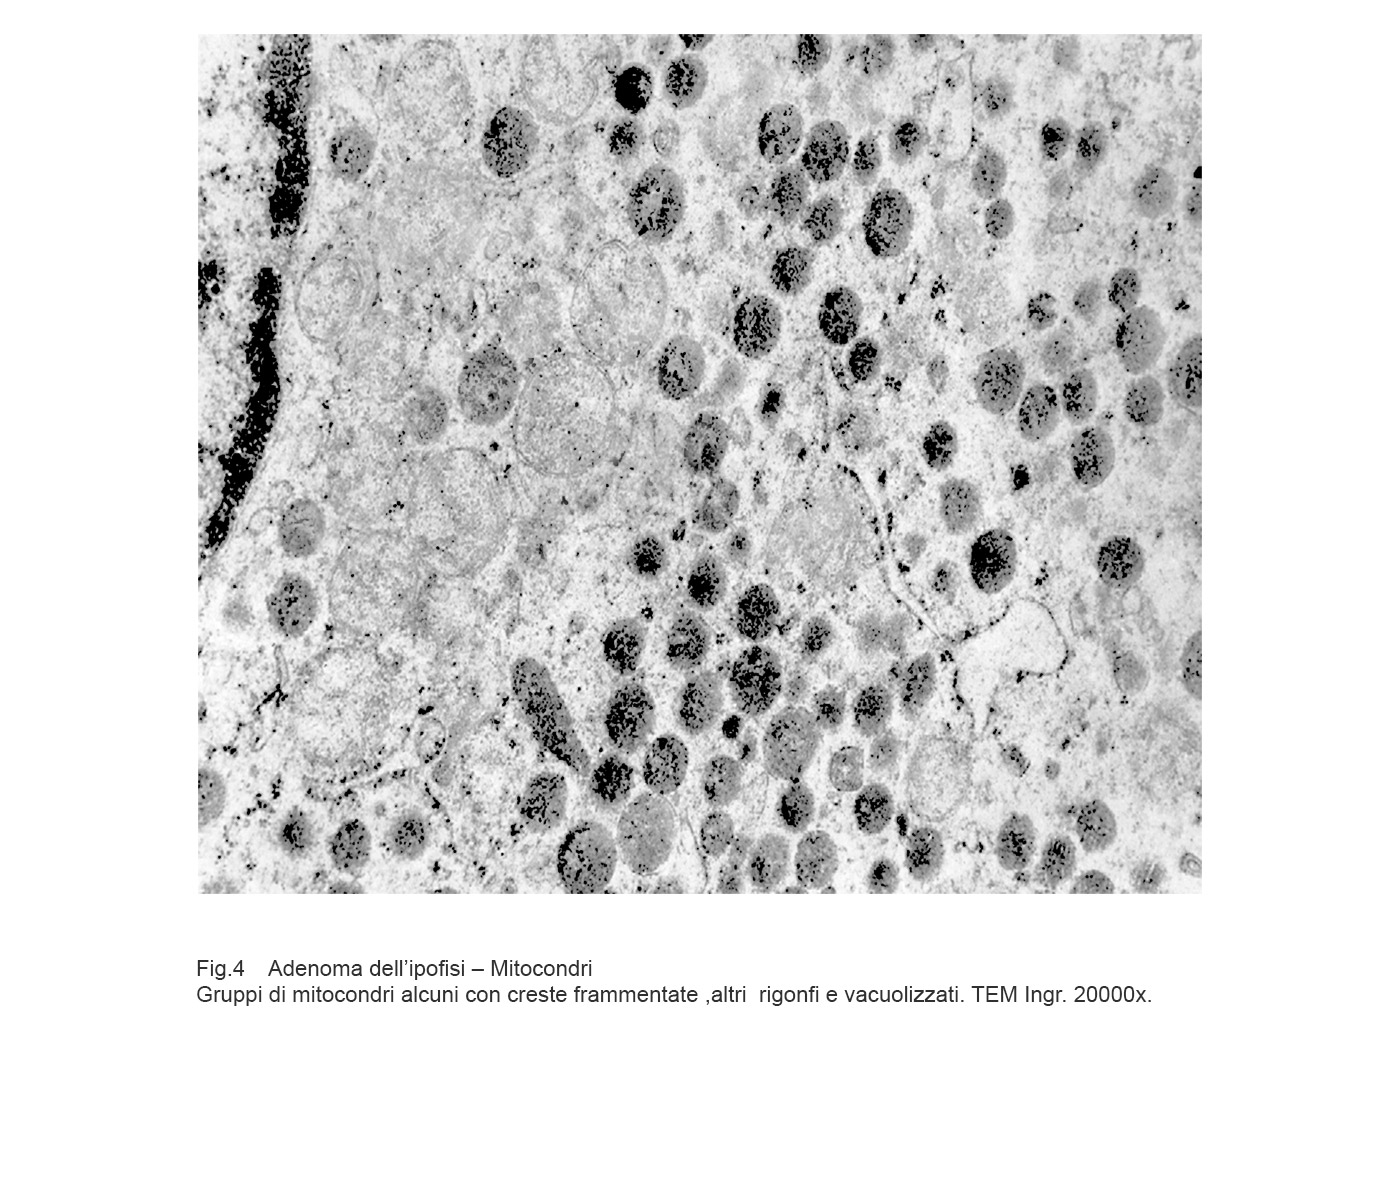

Cellule in attività secretiva le quali sono fornite di quote cospicue di mitocondri forniti di creste tubulari oppure di mitocondri rigonfi con creste in numero ridotto, spezzettate, disposte spazialmente in modo disordinato.

Fig.3  Fig.4

Fig.4